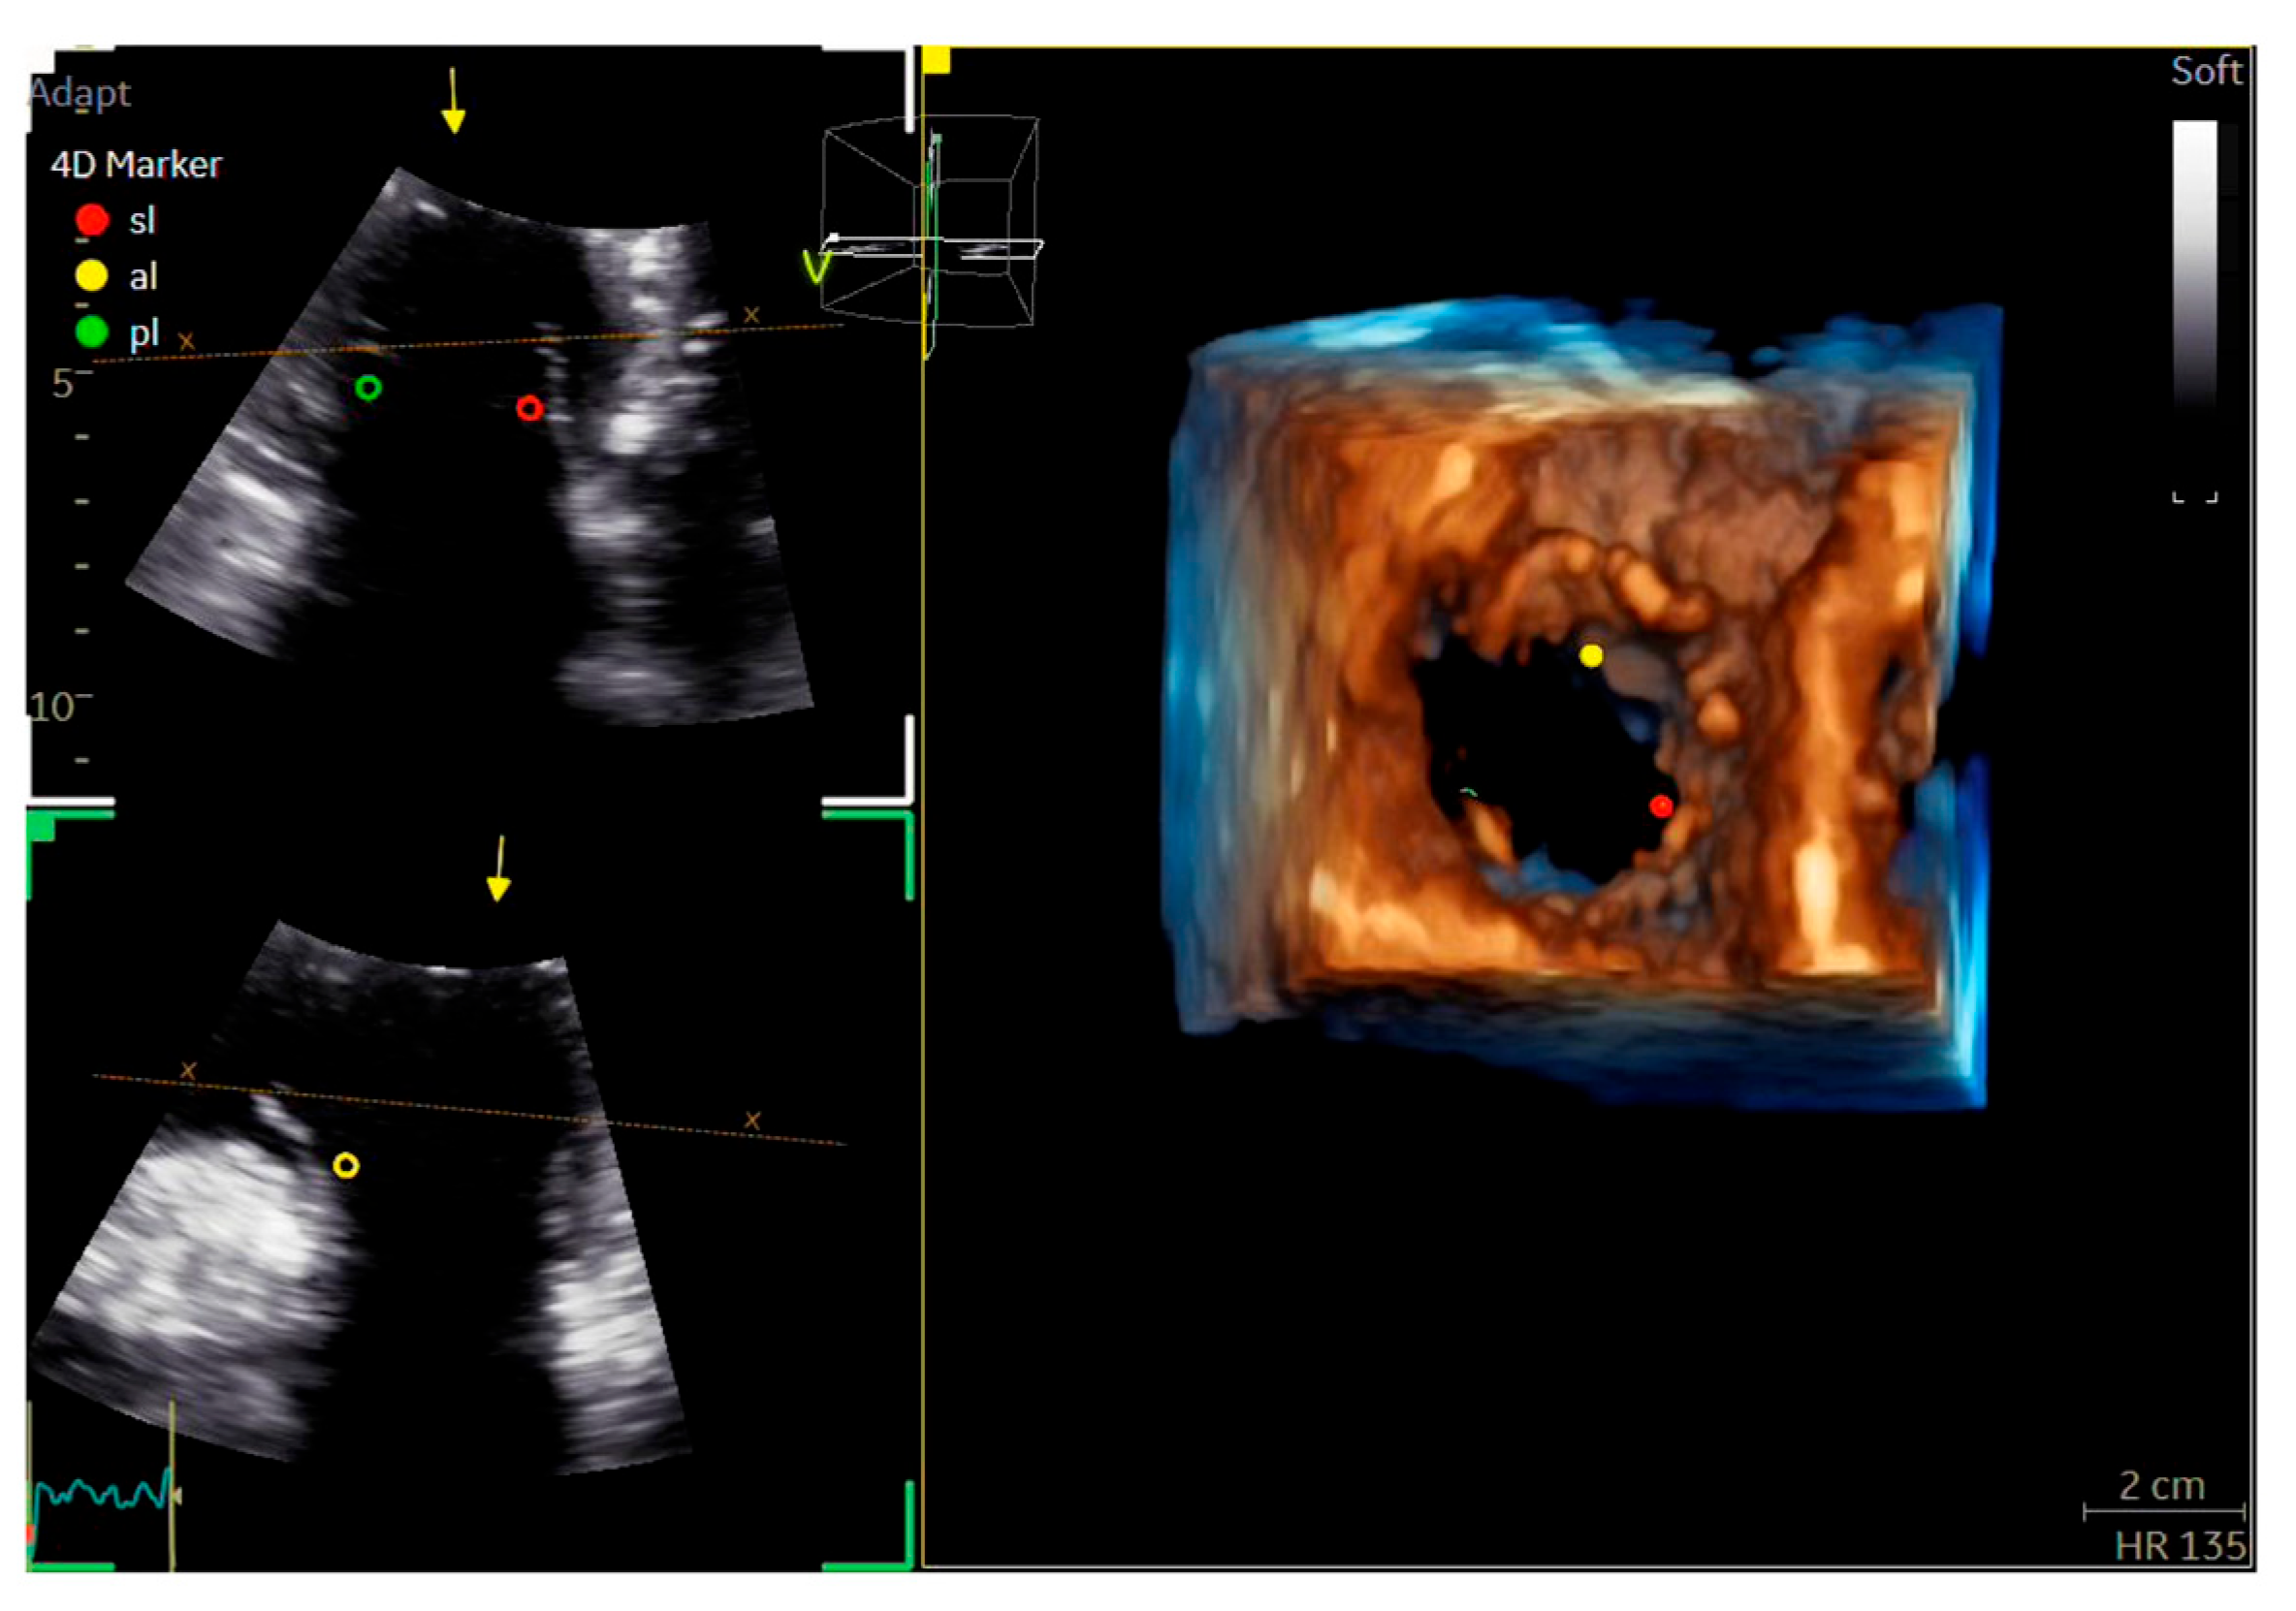

| Echocardiography (Figure 2, Figure 3, Figure 4 and Figure 5) |